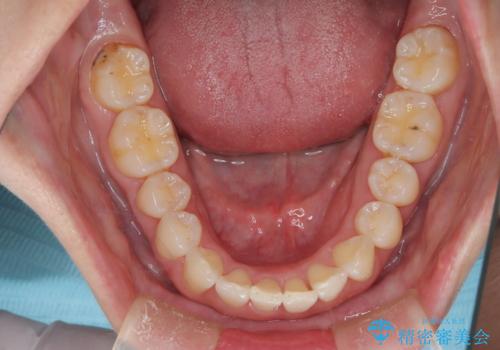

【モニター】処置歯の多い歯列 インビザラインでデコボコを整える